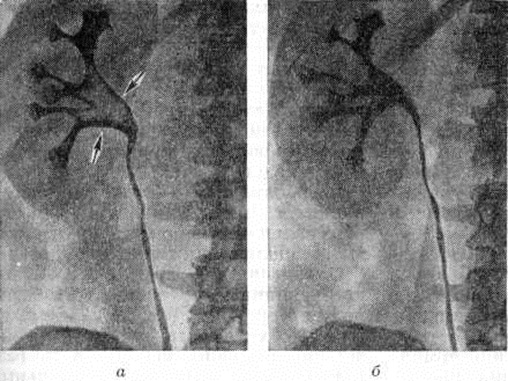

Рентгенологические метод является основным в диагностике Почечнокаменная болезнь Он позволяет выявить не только наличие камней, но и установить их форму, величину, локализацию, структуру, а также получить представление об изменениях в анатомо-функциональном состоянии почек и мочевых путей. Исследование начинают с обзорной рентгенографии брюшной полости, начиная от ThXl до лонного сочленения. Обнаружение на обзорной рентгенограмме тени, подозрительной на конкремент, не требует дифференциальной диагностики только в случае коралловидного камня, являющегося слепком чашечно-лоханочной системы (рисунок 2). Камни почечных чашечек представляют собой их слепки или имеют неправильную, округлую форму; камни почечной лоханки часто округлые или треугольные; камни мочеточника — цилиндрической, веретенообразной или неправильной формы. При аномалиях мочевых путей конкремент может находиться вне обычной локализации почек и других органов мочеполовой системы. Обнаружение камня на снимке зависит от его размеров, химический состава и локализации. Наиболее интенсивное изображение дают оксалаты, затем камни смешанного состава и фосфаты. Оксалаты имеют шиповидные, фестончатые контуры и напоминают тутовую ягоду. Коралловидные камни чаще всего компактны, но могут быть слоистыми, как и остальные конкременты смешанного состава, иногда они достигают гигантских размеров. Слоистое строение камней на рентгенограммах обусловлено различной проницаемостью для рентгеновского излучения составляющих их солей. Около 10% камней с низким атомным весом (ураты, белковые, цистиновые и ксантиновые камни) не видны или дают неотчётливую тень. Особенно трудно выявить камни, проецирующиеся на костный скелет (ребра, поперечные отростки позвонков, крестцово-подвздошные сочленения). Для их обнаружения производят прицельные снимки в косых и атипичных проекциях, томо или зонографию. Томография (смотри полный свод знаний), применяемая самостоятельно или в сочетании с контрастными исследованиями, показана при недостаточной подготовке больного к рентгенологическое исследованиям, почечной колике, сопровождающейся парезом кишечника, или при малых размерах камней. Поскольку при Почечнокаменная болезнь довольно часто конкременты самопроизвольно отходят из чашечно-лоханочной системы, они могут проецироваться по ходу мочеточника паравертебрально, имеют тенденцию задерживаться над одним из его анатомических сужений. Наиболее важные сведения о принадлежности выявленной тени к мочевым путям, о локализации камня, вызванных им нарушениях функции почек, уродинамики, анатомического состояния мочевых путей (гидрокаликоз, пиелэктазия, гидроуретеронефроз — расширение чашечек, лоханки, мочеточника и почки) выявляются при экскреторной урографии (рисунок 3, б) с предварительной обзорной рентгенографией (рисунок 3, а). Она позволяет установить вид лоханки (открытая или закрытая, внутрипочечная или внепочечная), состояние лоханочно-мочеточникового сегмента (смотри полный свод знаний: Пиелография). Обычно рентгенопозитивный конкремент определяется в мочевых путях, но иногда его изображение перекрывается, как бы тонет на фоне контрастированной мочи, особенно при небольшом камне или малой интенсивности его изображения. При рентгенонегативных камнях виден дефект наполнения мочевых путей (в том числе и лоханки) с чёткими контурами (рисунок 4). В отличие от опухоли лоханки в косых проекциях вокруг камня сохраняется ободок контрастного вещества. Обычно при камнях лоханки, достигающих в диаметре 3 сантиметров и более, наблюдаются пиелэктазия и гидрокаликоз. Произведённые в процессе экскреторной урографии телевизионная пиелоуретероскопия в сочетании с кинематографией или видеомагнитофонной записью изображения позволяют оценить нарушения тонуса и моторной функции верхних мочевых путей при камнях, отличить спастические, функциональный процессы от органических. Если спустившийся в мочеточник камень частично закрывает его, то отмечаются расширение мочеточника и лоханки (пиелоуретерэктазия) выше уровня расположения конкремента. На экскреторных урограммах, произведённых во время почечной колики, выявляется увеличенная почка с усиленным нефрографическим эффектом без контрастирования чашечно-лоханочной системы и мочеточника — так называемый большая белая почка. Такая рентгенологическое картина указывает, что функция почки сохранена. При длительной полной блокаде камнем (более 3—4 недель) функция почки из-за атрофии снижается и может полностью утрачиваться. На экскреторных урограммах, произведённых после почечной колики, иногда наблюдается проникновение контрастированной мочи за пределы мочевых путей, а также лоханочно-почечный рефлюкс. Ретроградную пиелоуретерографию с жидким контрастным веществом или кислородом производят только при значительном снижении функции почек, при сомнении в диагнозе, особенно в тех случаях, когда при экскреторной урографии не выявляется рентгенонегативный камень. Рентгенографию мочеточника после введения в него катетера производят в прямой и косой проекциях. Если при этом тень, подозрительная на камень, на обоих снимках находится рядом с катетером или сливается с его тенью, то диагноз Почечнокаменная болезнь не вызывает сомнений. Тень, не относящаяся к мочеточнику, определяется на некотором расстоянии от катетера. На ретроградных пиелограммах с жидким контрастным веществом небольшой концентрации рентгенонегативные камни выявляются в виде дефекта наполнения. Особенно демонстративными такие камни становятся при пневмопиелорентгенографии или пневмопиелотомографии (рисунок 5). С помощью ретроградной уретерографии удаётся выявить рентгенонегативный камень в мочеточнике, верхние границы дефекта при этом имеют вогнутую форму (рисунок 6).

Больным с уратными (рентгенонегативными) камнями при удовлетворительной функции почек и уродинамике, отсутствии острого пиелонефрита назначают так называемый растворители — препараты цитратов (магурлит, солуран и другие). Дозировка их индивидуальна и регулируется в процессе лечения в зависимости от pH мочи (необходимо поддерживать pH в пределах 6,2—6,9). Курс лечения 1½—2½ месяцев с последующим контрольным рентгенологическое исследованием. В ряде случаев лечение даёт положительный результат (рисунок 7). При отсутствии эффекта повторные курсы лечения нецелесообразны.